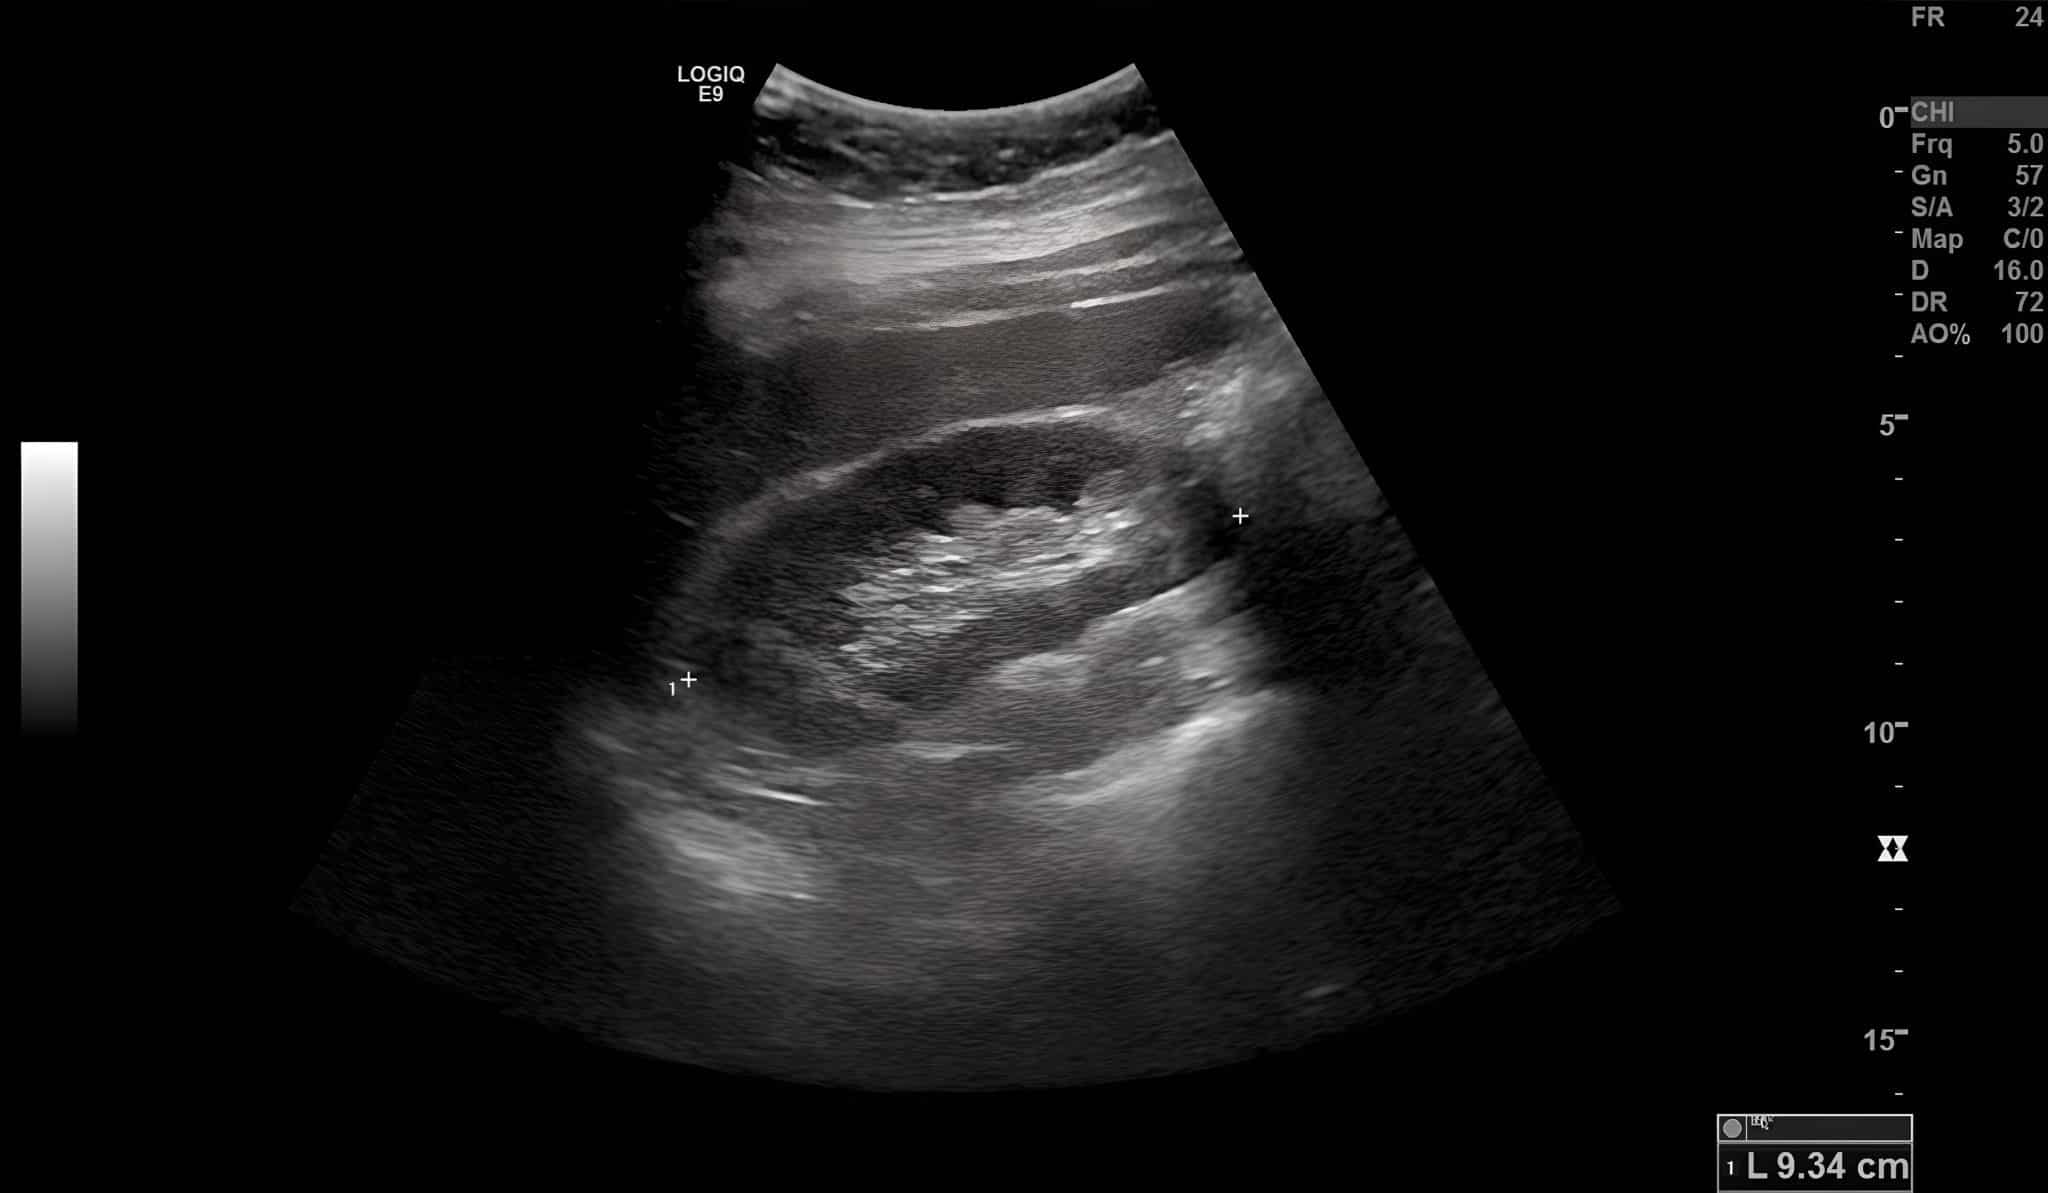

Многофункциональным тренажер состоит из внешнего модуля, имитирующего часть тела человека, и внутреннего содержимого — фантома почки с чашечно-лоханочной системой и окружающих тканей — костей, жировой и мышечной ткани и кожи. Все структуры получены путем трехмерного моделирования и воспроизведения с помощью уникальных тканеэквивалентных материалов, разработанных в Сеченовском Университете.

Тренажер также имеет несколько сменных картриджей — для отработки навыков пункции чашечно-лоханочной системы почки, проведения эндоскопических вмешательств, а также для диагностических и лечебных манипуляций на почке, пораженной опухолью. Оттачивать профессиональные умения хирурги смогут под контролем ультразвукового, рентгенологического, включая МРТ и КТ, и эндоскопического способов визуализации.